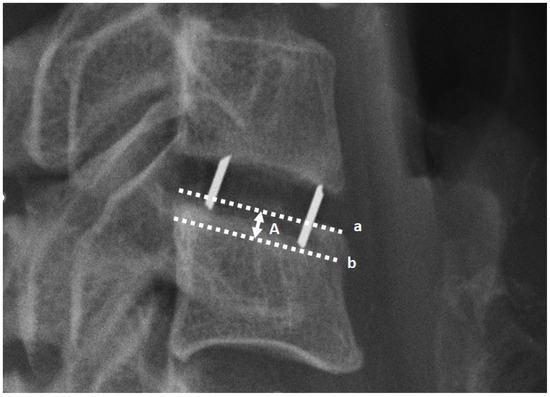

| Cage–endplate distance ratio 2 | Mean: | 0.22 | 0.17 | 0.29 | 0.18 | 0.15 |

| Coefficient: | Z = 1.53 a | H = 2.79 d | ||||

| p value | 0.1273 a | 0.2477 d | ||||

| Cage distance to endplate length ratio 3 | Mean: | 0.20 | 0.19 | 0.22 | 0.19 | 0.17 |

| Coefficient: | Z = −0.92 a | H = 2.24 d | ||||

| p value | 0.3602 a | 0.3255 d | ||||